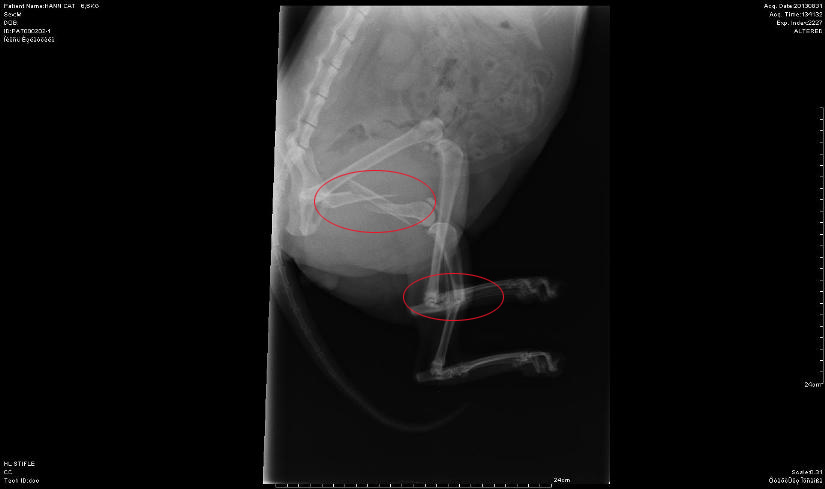

und brachte ihn sofort zum ansässigen Tierarzt. Bei den

Röntgenaufnahmen stelle sich heraus, dass das Bein sehr kompliziert

gebrochen war und vor Ort nicht gerichtet werden konnte. Hier das

Röntgenbild vom Tag des Unfalls: